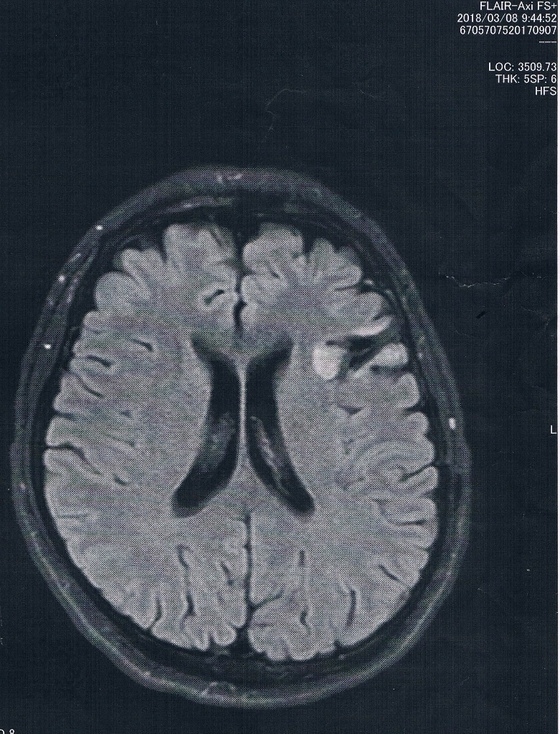

MRI検査の結果、半年前や一年前と比べても変化は無し!

今回2018/3/8(手術後45か月)のMRI画像